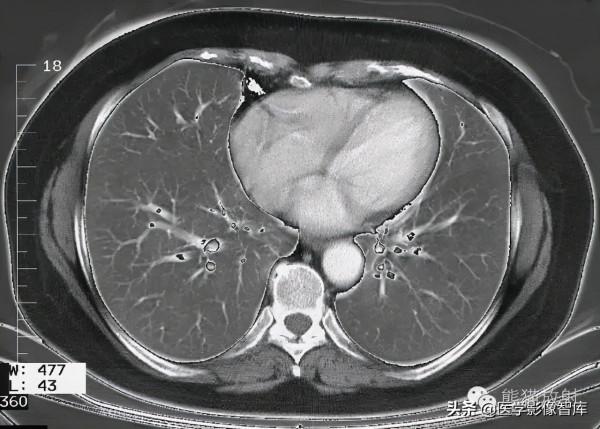

第十一層:四腔心水平

1. Latissimus dorsi muscle 背闊肌

2. Serratus anterior muscle 前鋸肌

3. Right lung 右肺

4. Right atrium 右心房

5. Internal thoracic artery and vein 胸內動脈、靜脈

6. Right coronary artery 右冠狀動脈

7. Right atrioventricular (tricuspid) valve 三尖瓣

8. Sternum (body) 胸骨體

9. Right ventricle 右心室

10. Interventricular septum 室間隔

11. Left atrium 左心房

12. Rib (costal cartilage) 肋軟骨

13. Left coronary artery (interventricular branch) 左冠狀動脈(室間支)

14. Left ventricle 左心室

15. Coronary sinus 冠狀竇

16. Left coronary artery (circumflex branch) 左冠狀動脈(迴旋支)

17. Phrenic nerve and pericardium 膈神經及心包

18. Myocardium 心肌

19. Rib 肋骨

20. Intercostal muscle 肋間肌

21. Azygos vein 奇靜脈

22. Erector spinae muscle 豎脊肌

23. Trapezius muscle 斜方肌

24. Spinal cord 脊髓

25. Spinous process 棘突

26. Esophagus食管

27. Sympathetic trunk 交感幹

28. Thoracic duct 胸導管

29. Descending aorta 降主動脈

30. Left lung 左肺

31. Paramammary lymph nodes

乳房旁淋巴結

32. Paravertebral lymph nodes

椎旁淋巴結

33. Lateral pericardial lymph nodes

心包外側淋巴結

34. Parasternal lymph nodes

胸骨旁淋巴結

35. Prepericardial lymph nodes

心包前淋巴結

36. Juxtaesophageal lymph nodes

食管旁淋巴結

37. Para-aortal lymph nodes

主動脈旁淋巴結

38. Intercostal lymph nodes

肋間淋巴結

Right Lung 右肺

4. Lateral segment of middle lobe

中葉內側段

5. Medial segment of middle lobe

中葉外側段

7. Medial basal (cardiac) segment of lower lobe

下葉內基底段

8. Anterior basal segment of lower lobe

下葉前基底段

9. Lateral basal segment of lower lobe

下葉外基底段

10 Posterior basal segment of lower lobe

下葉後基底段

Left Lung 左肺

5. Inferior lingular segment

下舌段

10. Posterior basal segment of lower lobe